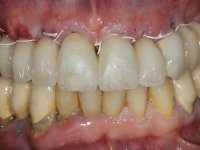

O paciente apresentou-se na consulta com intenção de fazer uma reabilitação estética e funcional completa.

Paciente do sexo masculino, com 64 anos de idade e não fumador. Apresentava uma prótese combinada superior composta por uma ponte metalo-cerâmica fixa de 6 elementos (1.3,1.2,1.1,2.1,2.2, e 2.3) e uma prótese esquelética superior também com 6 elementos. No maxilar inferior apresentava duas pontes metalo-cerâmicas, uma de 3 elementos no 4º quadrante e outra de 2 elementos no 3º quadrante. A adaptação das pontes estava comprometida e esteticamente não satisfaziam o paciente. A higiene oral não era satisfatória.

Foi proposto ao paciente fazer uma reabilitação total superior sobre implantes com colocação de uma prótese provisória aparafusada em carga imediata. Após osteointegração seria colocada uma prótese fixa metalo-cerâmica, se possível, com fixação aparafusada. No maxilar inferior foi proposta a colocação de 3 implantes no 4º quadrante para suportar uma ponte metalo-cerâmica de 3 elementos.